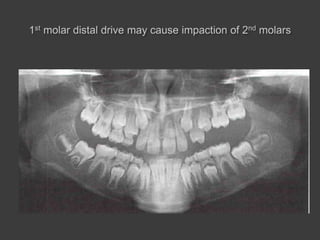

(2) Posterior dimension or limitation

 The posterior dimension of the mouth is important to

note that when non-extraction treatment is touted ,

32 teeth must be maintained in the mouth.

 The extraction of third molar is a therapeutic decision .

 If a patient has to have third molar extracted , it is

extraction treatment , not non-extraction treatment.

 The non-extraction treatment cannot be performed if the

second molars are hopelessly impacted.